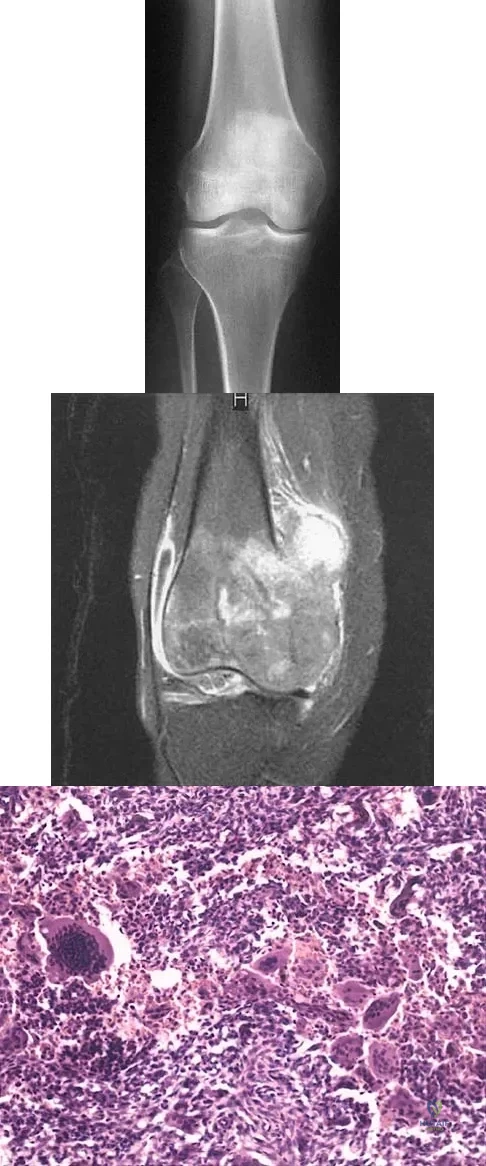

A 16-year-old girl has had anterior leg pain and a mass for the past 8 months. Figures 2a and 2b show a radiograph and an H & E histologic specimen. Which of the following disorders is believed to be a precursor of this lesion?

A 21-year-old man has had progressive right knee pain for the past 2 months that is exacerbated with weight-bearing activities. A plain radiograph and an MRI scan are shown in Figures 43a and 43b. A biopsy specimen is shown in Figure 43c. According to the Enneking staging system of tumor classification, the lesion should be classified as what stage?